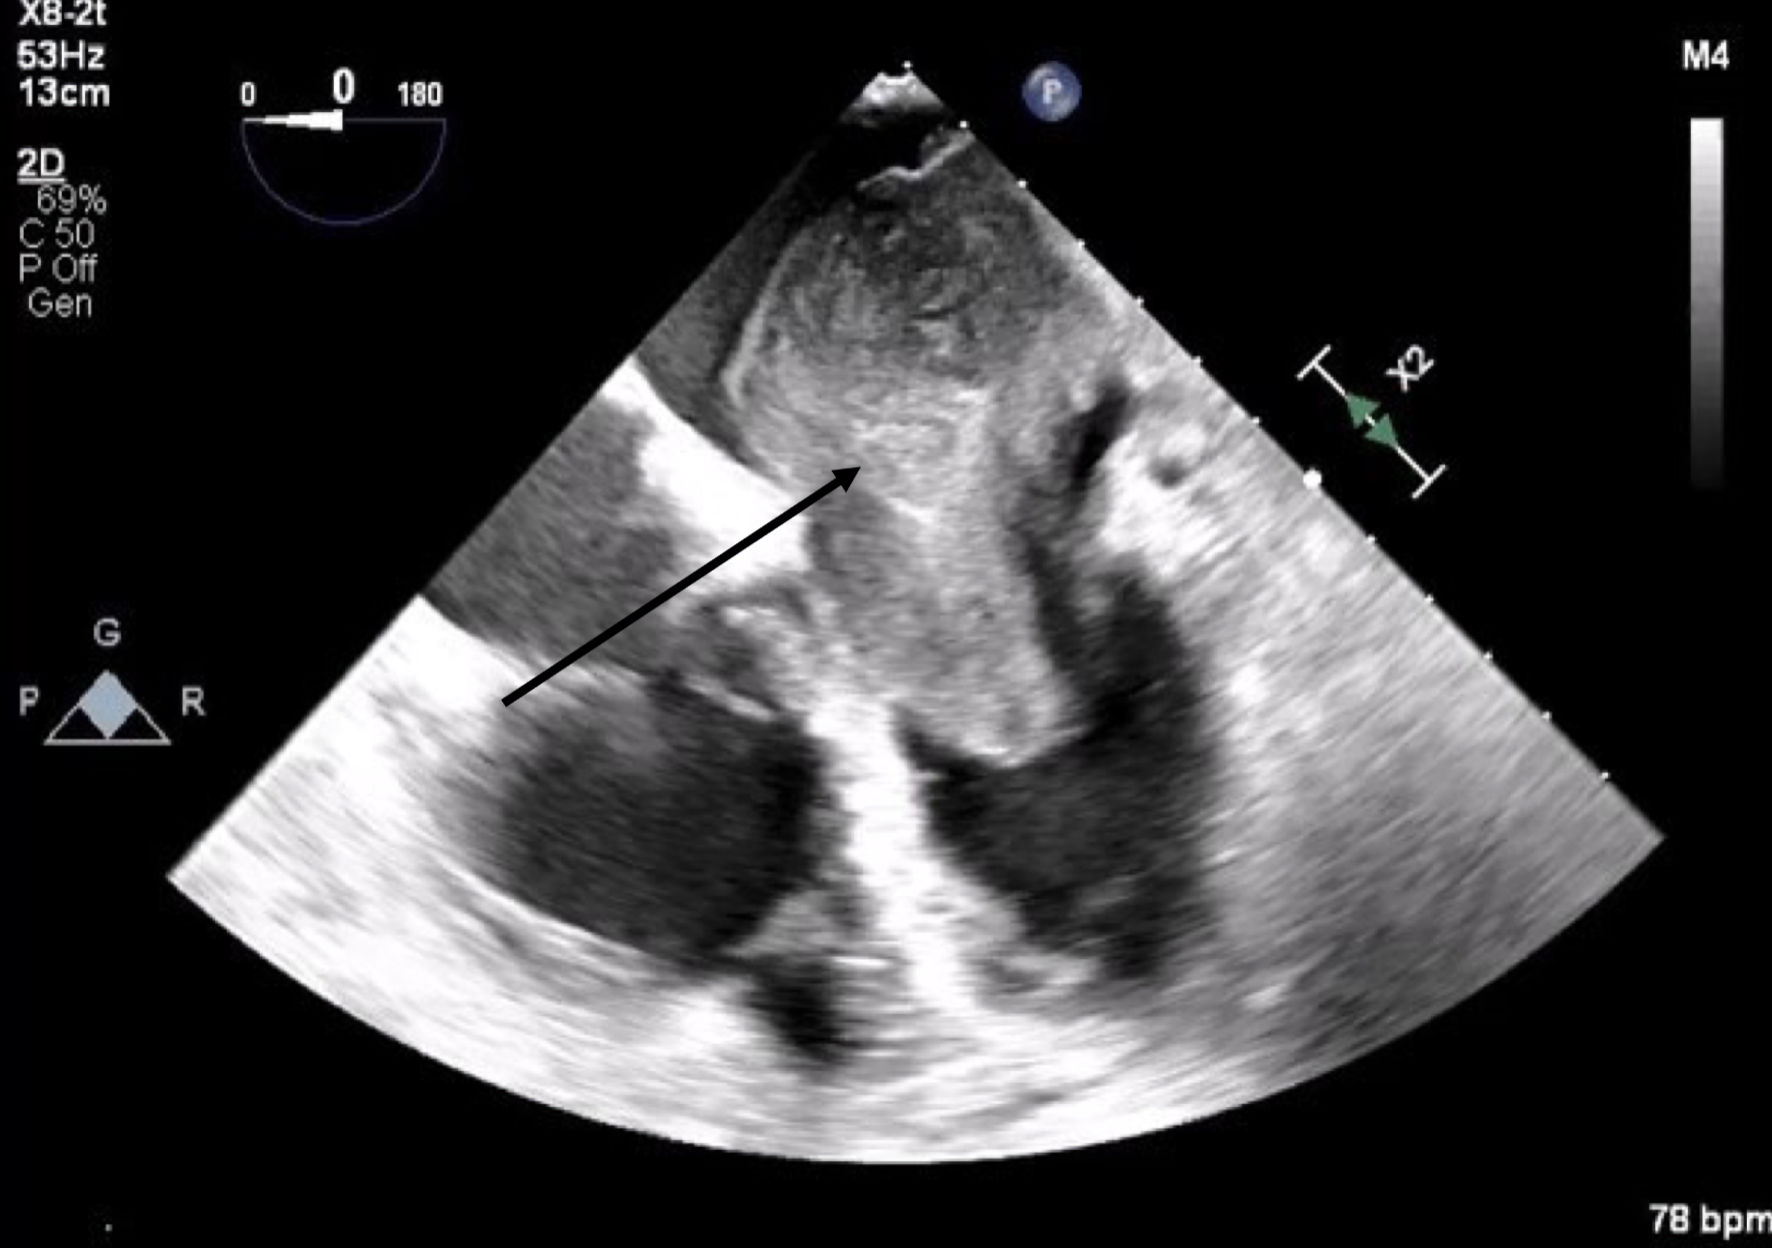

A 66-year-old obese woman presented to the emergency department (ED) with a 2-month history of progressive fatigue, 20-lb weight loss, orthopnea, wheezing, chest pressure, lower extremity edema, dyspnea on exertion, and paroxysmal nocturnal dyspnea. On examination, she had a systolic murmur. Transthoracic echocardiography (TTE) revealed a 5-cm mass occupying her left atrium. Right and left heart catheterization showed no flow-limiting coronary artery disease. Right heart pressures were as follows: right atrium 3 mm Hg, right ventricle 66/4 mm Hg, pulmonary artery 67/25 mm Hg, pulmonary capillary wedge pressure 25 mm Hg, and left ventricle 103/9 mm Hg. With plan for further workup, she was discharged and scheduled for elective resection. She returned to the ED 5 days later with severe acute hypoxic respiratory failure. On admission, vitals were as follows: heart rate (HR) 129, respiratory rate (RR) 44, SpO2 92%, and blood pressure (BP) 110/70. Her hypoxemia was managed with high-flow nasal cannula, and she was scheduled for urgent resection of her left atrial mass. In the operating room, she was severely orthopneic when the head of her bed was lowered below 90°. A radial arterial and internal jugular central venous catheter were placed while she was in a seated position on high-flow nasal cannula (fraction of inspired oxygen (FiO2) 100%, 35 liters per minute (LPM)). Femoral central venous and arterial cannulas were also placed prior to induction of anesthesia to enable emergent transition cardiopulmonary bypass (CPB). A dexmedetomidine infusion was used to facilitate vascular cannulation, surgical preparation, and draping. Vasopressin, epinephrine, and norepinephrine infusions were started preemptively, and she received a 250-mL albumin bolus. Her airway was secured with video laryngoscopy after induction with etomidate and rocuronium. After induction, she became profoundly hypotensive and hypoxemic, with mean arterial pressure (MAP) dropping by 30 mm Hg and oxygen saturation dropping to 70%. This brief episode resolved with administration of crystalloid, vasopressin boluses, and Trendelenburg positioning. Despite a transient period of hypotension and hypoxia, emergency CPB was not required. A median sternotomy was performed, and she was transitioned to CPB by aorto-bicaval cannulation. Intraoperative transesophageal echocardiography (TEE, X8-2t, EPIQ CVx; Philips Ultrasound, Bothell, WA) redemonstrated a large pedunculated mass traversing the interatrial septum and occupying the right and left atria. Mid-esophageal views were used to image the large heterogeneous mass (Figs. 1, 2). She was found to have a 7 × 4.5 cm left atrial mass arising from the lateral wall of the atrium near the left inferior pulmonary vein. Pulmonary venous return was obstructed, likely contributing to her pulmonary hypertension, pulmonary edema, and hypoxemia. During atrial systole, the mass traversed the mitral valve orifice and obstructed mitral inflow and the left ventricular outflow tract (LVOT). LVOT obstruction persisted during early ventricular systole, and flow acceleration was observed with color flow doppler (Figs. 3-5).

Figure 1. Mid-esophageal four-chamber view. A mass with lateral wall stalk prolapses through mitral valve during diastole. The arrow denotes the large cardiac tumor.

Figure 2. Mid-esophageal four-chamber view. A mass occupies the majority of the left atrium during systole. The arrow denotes the large cardiac tumor.